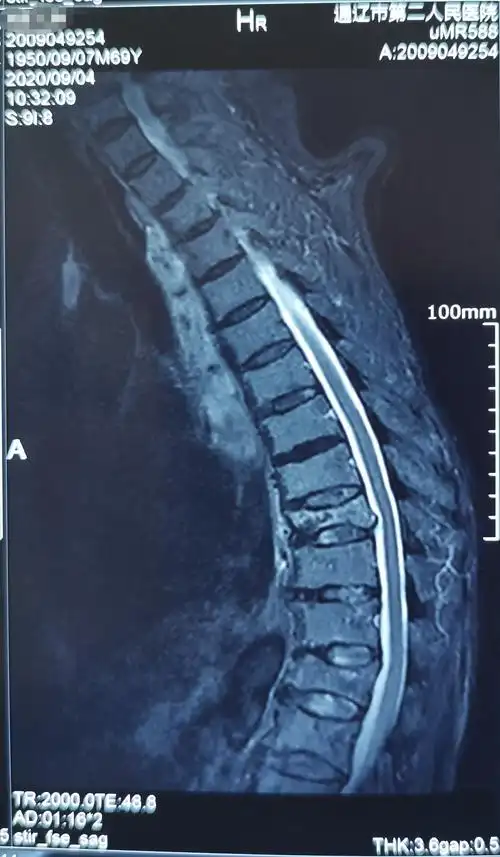

71岁胸9压缩性骨折椎体成型手术一例